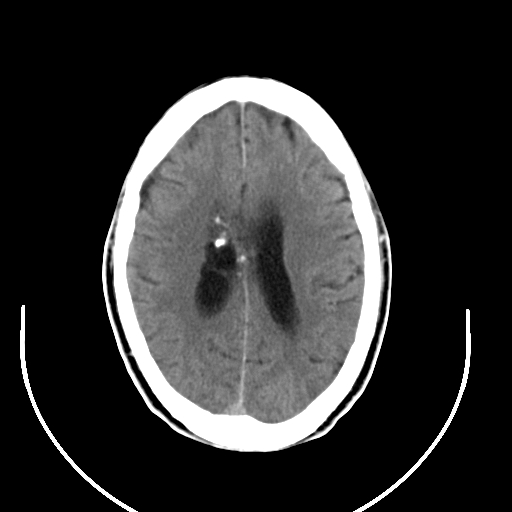

以下是引用拾荒者在2008-7-26 15:36:00的发言:[br]侧脑室内高密度钙化影,未见软组织结构,侧脑室未见增大,考虑良性钙化性改变(钙化型脑膜瘤可能)。

以下是引用宇宙ct在2008-7-26 13:43:00的发言:[br]支持:钙化性脑膜瘤。 不排除脉络膜瘤 [br] [br]